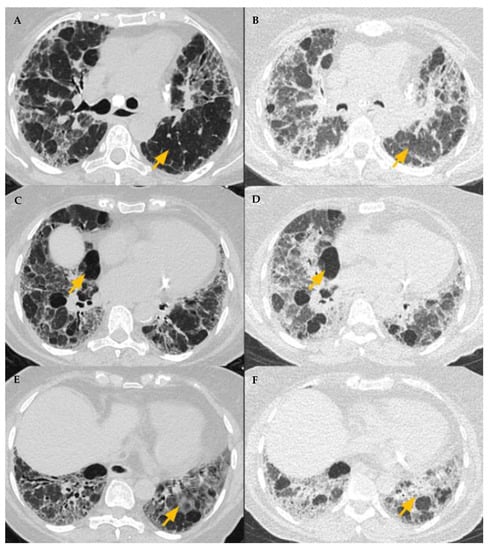

| Typical HP Pattern (Suggests a Diagnosis of HP) | Compatible with HP | Indeterminate for HP |

|---|---|---|

| At least one finding indicative of small airway disease | At least one finding indicative of small airway disease | Neither Typical nor Compatible with HP |

| Three-density pattern | Three-density pattern | HRCT Patterns: UIP pattern Probably UIP pattern Indeterminate for UIP Fibrotic NSIP pattern OP like pattern Truly indeterminate pattern |

| Air trapping | Air trapping | |

| Ill-defined <5 mm centrilobular nodules | Ill-defined <5 mm centrilobular nodules | |

| At least one finding indicative of pulmonary fibrosis | Variant pattern of fibrosis | |

| Coarse reticulations with distortion | UIP pattern of fibrosis | |

| Traction bronchiectasis | Extensive GGO and superimposed subtle fibrosis | |

| Honeycombing (not dominant) | ||

| Distribution of findings | Variant distribution of fibrosis | |

| Random axially and craniocaudally | Craniocaudal: Upper lung zone predominant | |

| Mid zone predominant | Axial: peribronchovascular, subpleural | |

| Relative sparing of the bases |